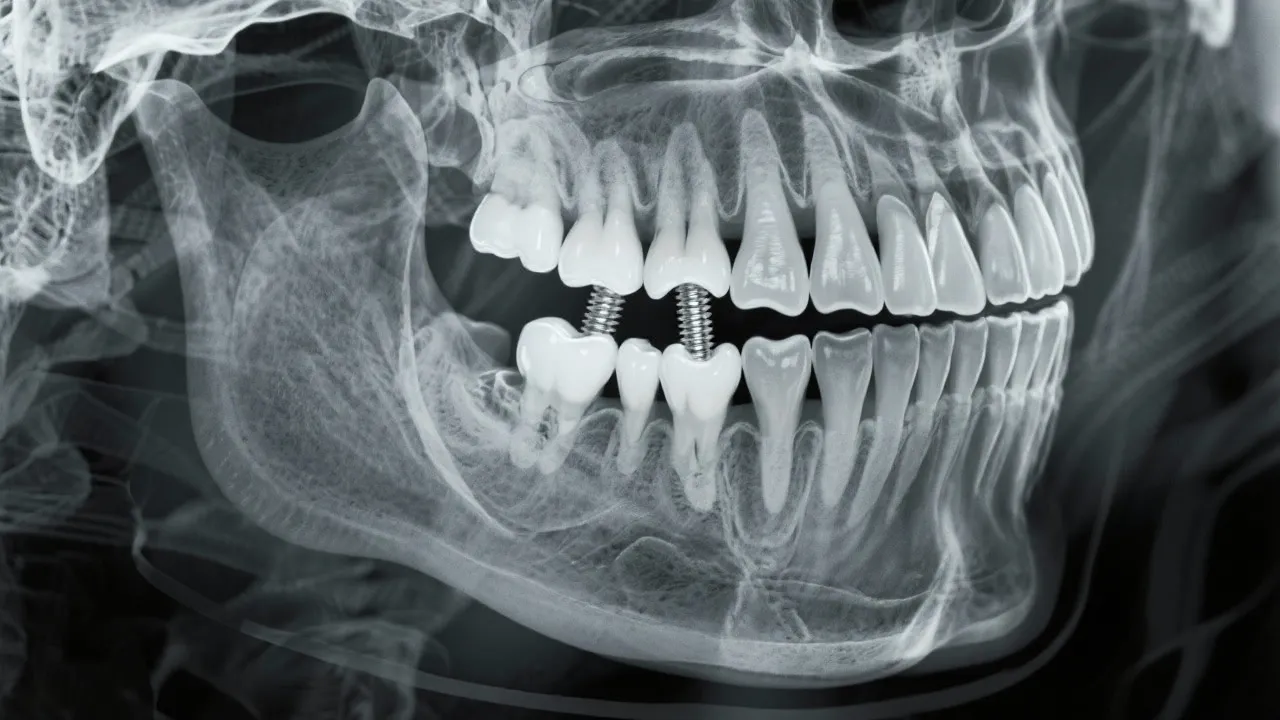

Bone density is a critical factor when considering dental implants. It refers to the amount of bone material present in a specific volume of bone, which directly impacts an implant's stability and longevity. Adequate bone density ensures that the dental implant can support the forces of chewing and other oral functions. Inadequate bone density, however, may lead to complications, affecting the implant's success rate. High bone density provides a stronger anchorage point, which is essential for the integration of the implant within the jawbone. When evaluating candidates for dental implants, dentists often conduct imaging studies like X-rays or CT scans to assessbone density patterns and bone structure.

Impact of Bone Density on Implant Success

In cases where bone density is questionable, preemptive measures such as bone grafting or the use of mini implants may be considered. Mini implants, which are narrower in design, can sometimes be placed without extensive grafting procedures; however, they may not be suitable for all patients or types of restorations. Collaborating closely with your dental team can help to devise the best approach tailored to your specific situation.